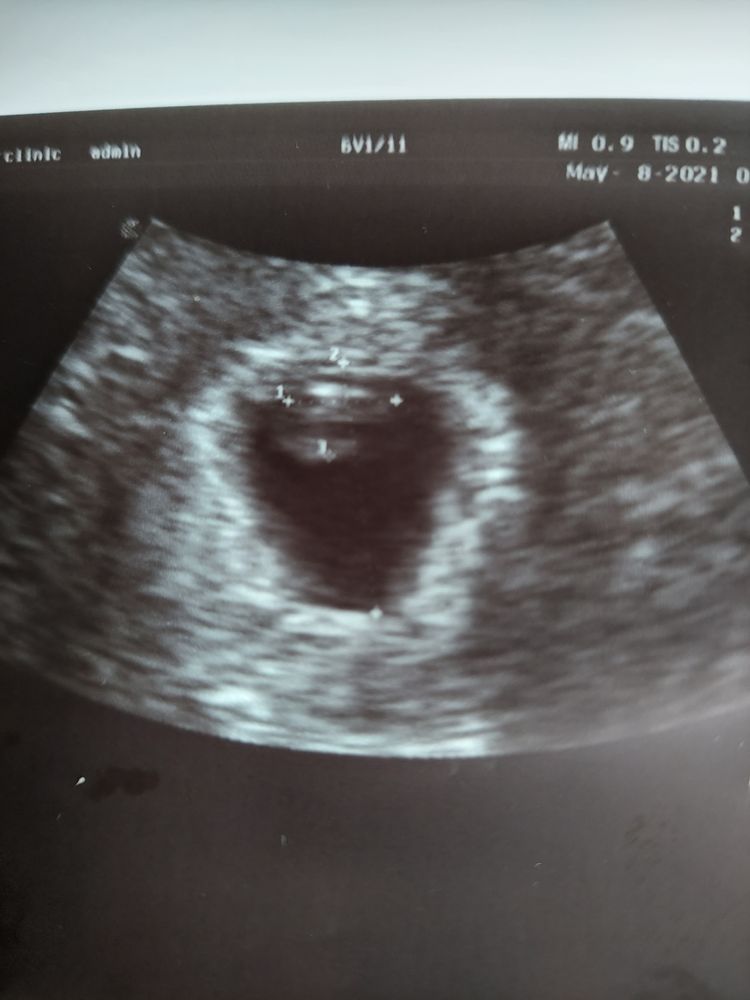

У вас не понятно ,по середине,а это мое УЗИ на 7 неделе

у меня не вагинальное по этому получается зеркально ,девочки слева мальчики справа ,вроде девочка на что я очень надеюсь ,позже проверим:)

Короче долго я гуглила и по ходу похоже на мальчика😃 проверим, работает ли теория😏

Плацента позже формируется. По этому методу смотрят прикрепление хориона, не плаценты) По поводу пола не знаю, я в этом методе не разбираюсь, вечно путаю 😁

Чашка утреннего кофе, прикрепление не меняется. Сначала хорион, а потом станет плацента. Но на фото вообще не понятно где и что прикрепилось 🤭

Женечка, ну вообще да, по сути хорион и есть будущая плацента) Ничего непонятно - это да😅